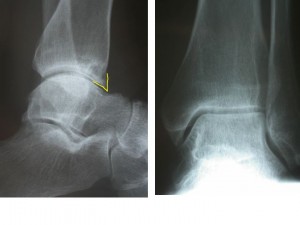

Eylül 3, 2014Futbolcu ayak bileği-Footballer’s ankle

Özellikle futbolcularda görülen, ayak bileğinin ön tarafında, ayak bileği eklemini öne en son noktaya getirildiğinde hissedilen batma, ağrı ve yanma ile karakterli bir ağrıdır.

Sürekli topa ayak sırtı ile vurma sonucu ayak bileği ön kapsülünün zorlanması nedeni ile ortaya çıkar. Bu bölgede kemikleşmeler oluşunca hastada ayak bileği hareketlerinde ağrı başlar.

Tıbbi tedavi ve fizyoterapi ile iyileşmeyen sporcuda ayak bileği artroskopisi kesin çözümdür.